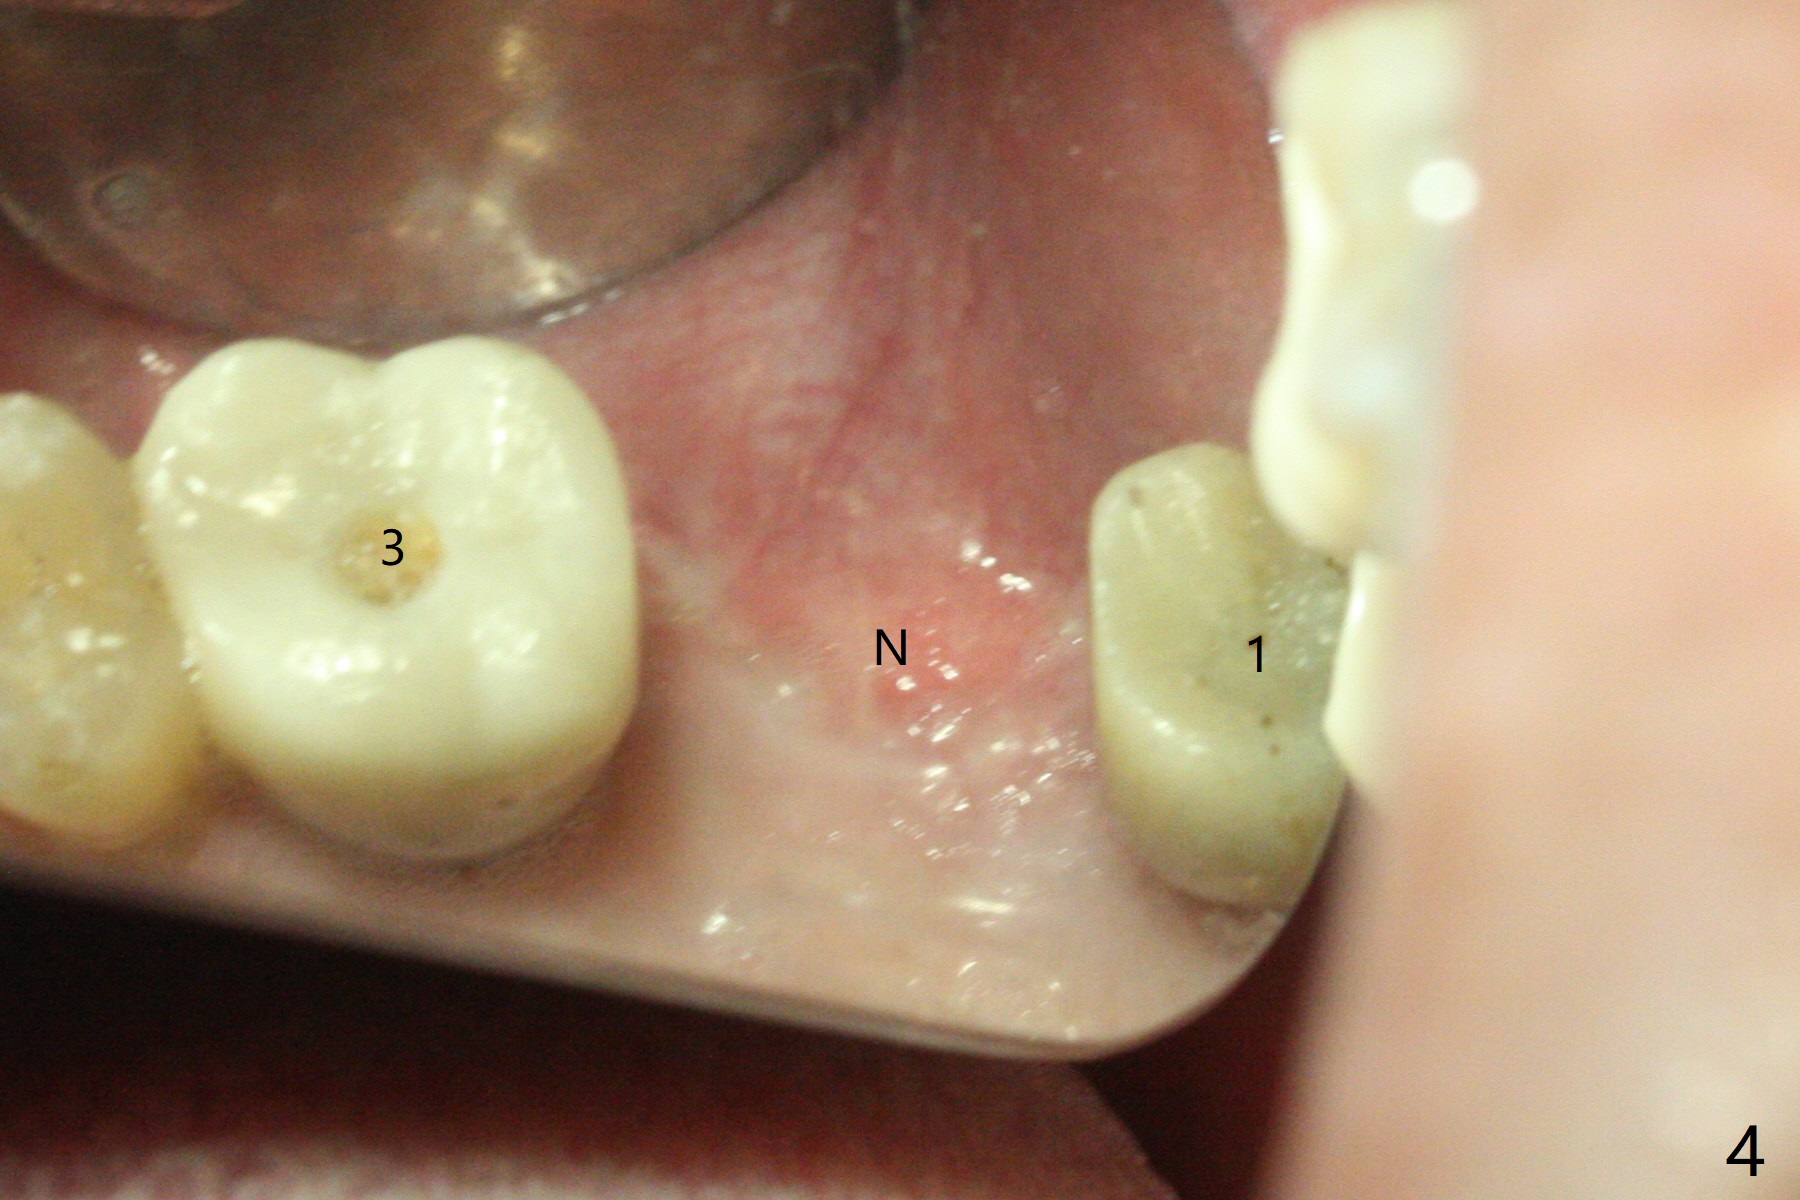

Removal of the implant at #2 is extremely difficult because of fusion of the abutment with the implant.  Buccal and palatal incisions are made to remove the bone buccomesiodistal to the implant.  After implant removal, the exposed mesial coronal implant threads at #1 are cleaned with Titanium brush; allograft is placed against the exposed threads (Fig.1 *), followed by 2 pieces of PRF membrane and 6-month collagen membrane.  Periodontal dressing is applied after suturing.  Partially due to traumatic implant removal and partially due to easy and repeated loss of periodontal dressing, bone height reduces nearly 4 months postop (compare Fig.2,3).  More discouraging is the invasion of loose nonkeratinized buccal gingiva into the healed socket nearly 4 months post graft (Fig.4 N).  Tissue punch thorough a guide should expose the implant site to the nonkeratinized tissue.  Can we fabricate a guide with buccal clearance underneath so that a flap can be raised buccally, i.e., to push the palatal keratinized tissue buccally?